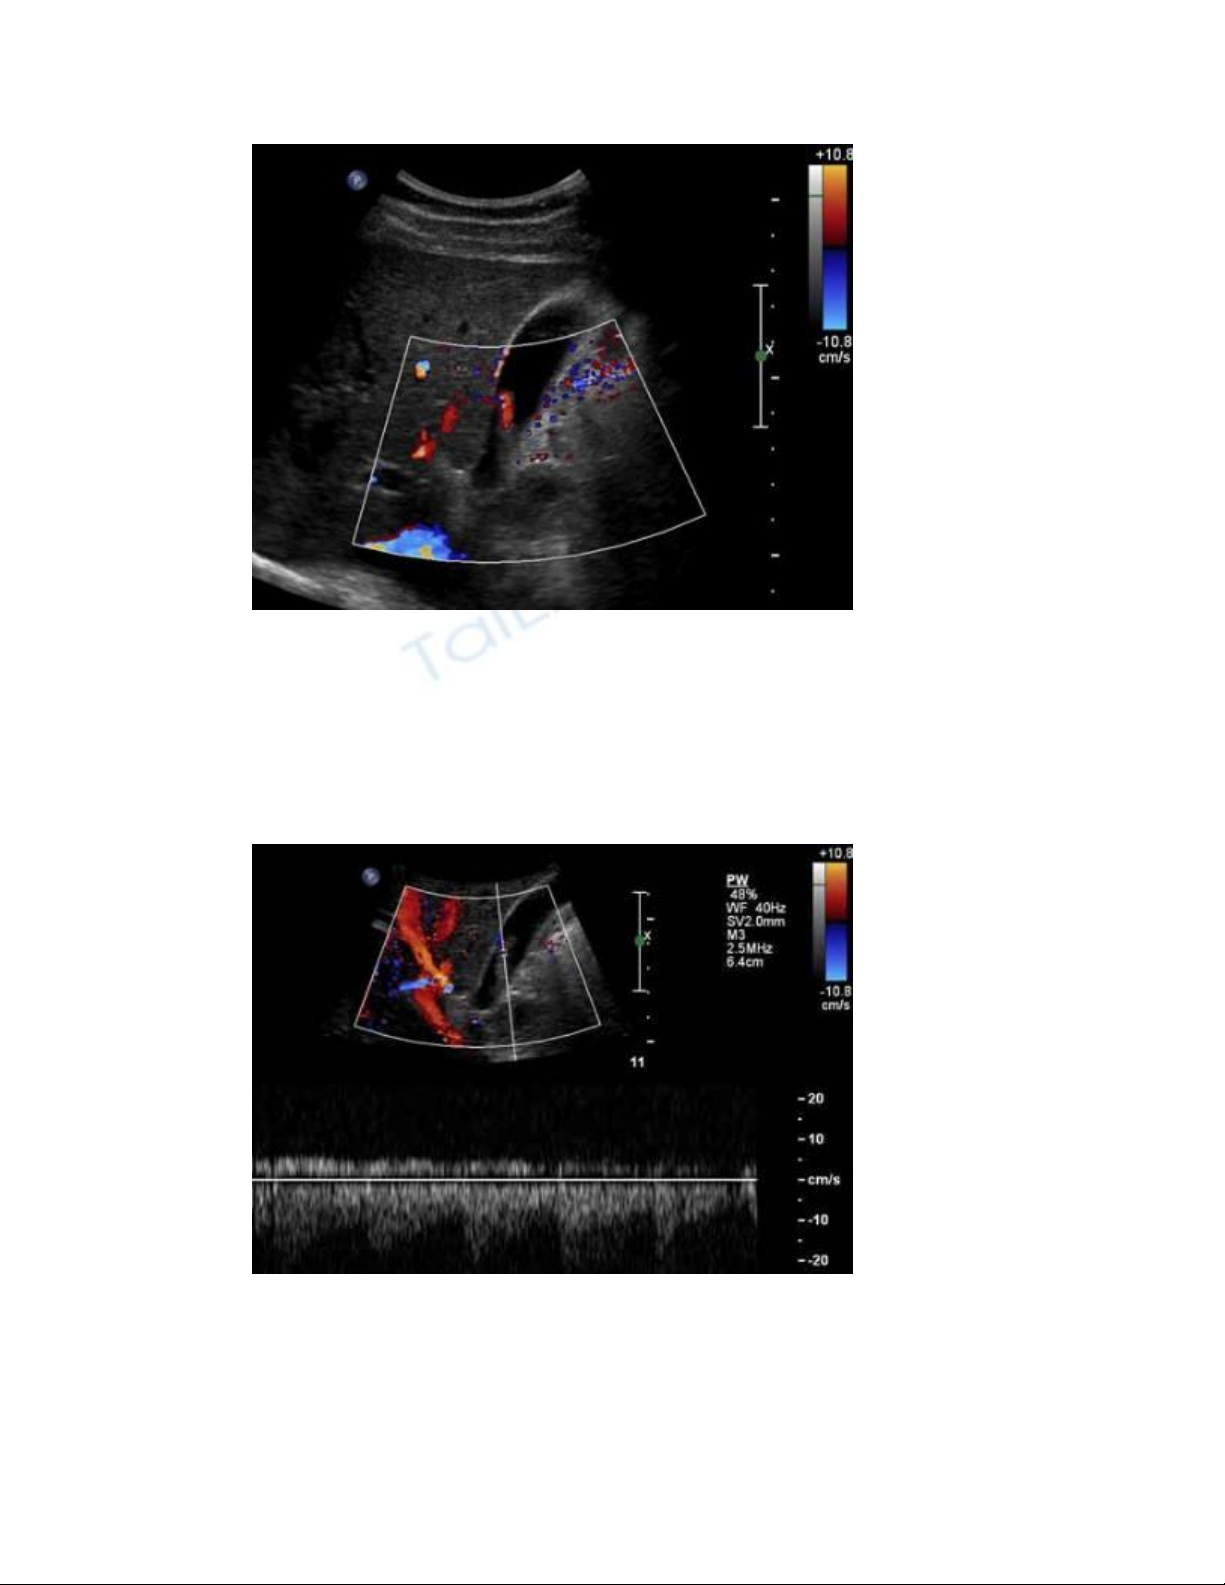

Hình cắt dọc túi mật với Doppler màu

Doppler màu cho thấy có dòng chảy bên trong khối này.

Hình cắt dọc túi mật với Doppler xung

Doppler xung xác nhận có cả dòng chảy của động mạch lẫn tĩnh mạch bên

trong khối.